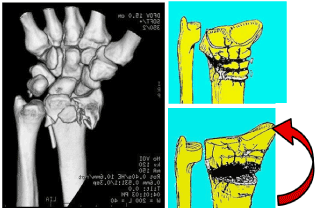

Laulan and Bismuth classification [12] (Figure 9).

Figure 9. Laulan and Bismuth classification. A simple and predictive analysis grading the metaphyseal rupture, the epiphyseal comminution and the distal ulna break